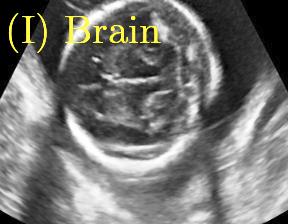

Sound-opaque occluders, including bones and calcified tissues, block the propagation of sound waves by strongly absorbing or reflecting sound waves during scanning. The regions behind these sound-opaque occluders return little to no reflections to the US transducer. Thus these areas have low intensity but very high acoustic impedance gradients at their boundaries (e.g. Fig. 1(a) left column). Reducing acoustic shadows and correct interpretation of images containing shadows rely heavily on sonographer experience. Experienced sonographers avoid shadows by moving the probe to a more preferable viewing direction during scanning or, if no shadow-free viewing direction can be found, a mental map is compounded with iterative acquisitions from different orientations.

We propose a novel method based on convolutional neural networks (CNNs) to automatically estimate pixel-wise confidence maps of acoustic shadows in 2D US images. Our method learns an initial latent space of shadow regions from images consisting of multiple anatomies and with global image-level labels (“has shadow” and “shadow-free”), e.g. Fig. 1(a). The basic latent space is then estimated by learning from fewer images of a single anatomy (fetal brain) with coarse pixel-wise shadow annotations (approximately of the images with global image-level labels), e.g. Fig. 1(b). The resulting latent space is then refined by learning shadow intensity distributions using fetal brain images so that the latent space is suitable for confidence estimation of shadow regions. By using shadow intensity information, our method can detect more shadow regions than the coarse manual segmentation, especially relatively weak shadow regions.

Row I in Fig. 6 shows a fetal brain image from . The confidence estimation of shadow regions from the baseline, the proposed method and the proposedAG method are similarly accurate since we use fetal brain images to train the confidence estimation networks in these three methods. These outperform [16] and [22]. Rows (II-IV) in Fig. 6 show shadow confidence maps of non-brain anatomy from , including lips, abdominal and cardiac. The baseline failed on unseen data during inference. However, the proposed methods are able to generate accurate shadow confidence maps because of the generalized shadow features obtained by the shadow-seg module. Furthermore, the “Lips” example shows that our method is capable of detecting weaker shadow regions that have not been annotated in manual segmentation. This indicates that the confidence estimation network has learned general properties of shadow regions.